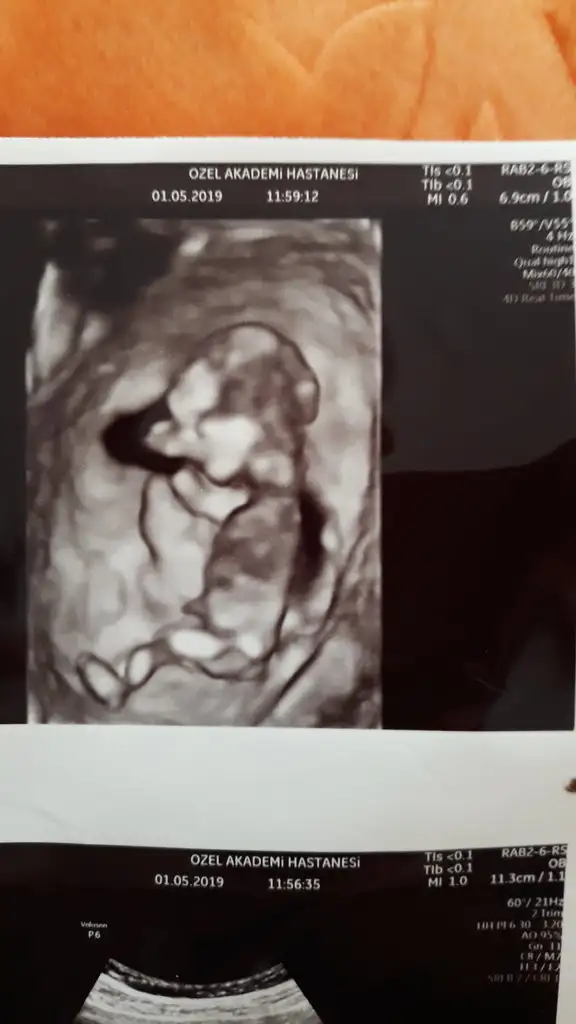

canım gözün aydın maşallah sevindim senin adına :) kız gibi dediyse kızdır çünkü 13+2 kocaman olmuş:)Kızlar ancak fırsat buldum yazmaya

Kontrolden çıktık sata gore 12+4 ultrasona gore geriden gelen bebişim bugun 13+2 cikti :) boyu 6.5 cm olmuş ense ve burun kemiğine iyi dedi kac diye sorunca 1den kucuk merak etme sorun yok dedi doktorumkan verdim 1 hafta sonra çıkacakmış sonuç doktorum cinsiyetle ilgili de kıza benziyor ama kesin değil dedi ve ben basından beri kiz hissediyorum:) en son gittiğimde mercimek tanesi kadardı ama bugun gercekten bir bebek gordum zıplayan kayan ellerini oynatan, Rabbimin gerçekten bir mucizesi Allahım hepimize boyle guzel haberler almayi nasip etsin inşallah tekrar :)Eki Görüntüle 2264270 Eki Görüntüle 2264272 Eki Görüntüle 2264270 Eki Görüntüle 2264272